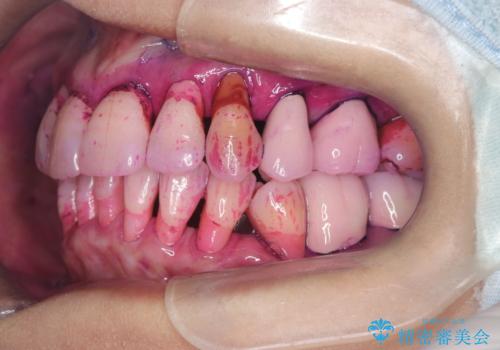

- 歯周病で歯茎が下がり根っこの部分が見えている状態で3か月のメンテナンスをコンスタントに通われている方です。

ブラッシングは歯間ブラシや部分歯ブラシなどの補助道具も使用し時間をかけて丁寧に磨いていらっしゃるのですが、ブラッシング圧に気を付けながらの為バイオフィルムが根っこの部分に残っているのです。

いつも時間をかけて丁寧に磨いていらっしゃるようですが染め出しをしてみると歯茎が下がっている部位はバイオフィルムの付着が見られました。

患者さまに説明してエアーフロー施術しこれから定期的に施術希望になりました。